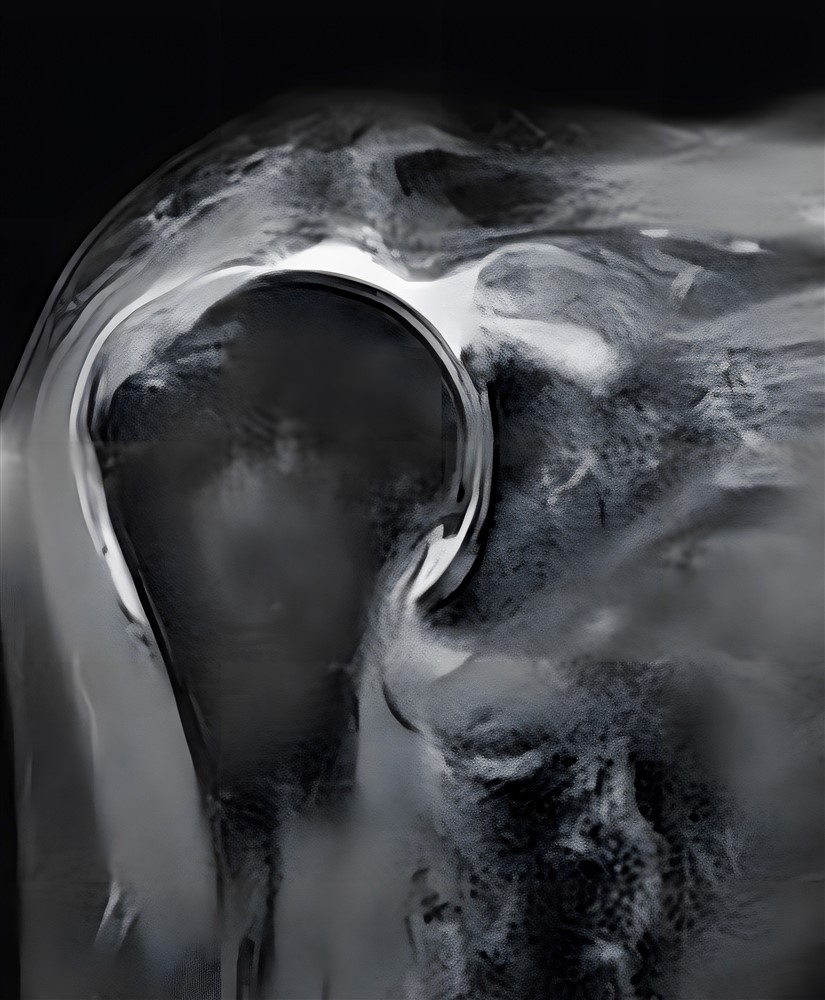

七十三歲病人經核磁共振影像檢查,顯示旋轉肌袖斷裂面積大片破損。

曾有一位七十三歲女士,右側肩膀疼痛無力一年多,右手臂僅能外展六十度就無法抬舉,一旦手臂放下右肩就劇痛無比。更可怕的是晚上休息及睡覺,肩膀也會隱隱作痛。不僅嚴重影響睡眠品質,許多生活自理的動作像是洗頭、洗臉或是伸手取物等都無法辦到。

經謝尚霖醫師門診檢查診斷為「右肩大片旋轉肌袖破裂合併肩關節軟骨磨損」,因為旋轉肌腱斷裂面積大而且肌肉組織都已嚴重脂肪性變化,以致無法修補。肩關節炎軟骨磨損確實會造成疼痛,病人在醫師建議下接受「反置式人工肩關節置換手術」,手術後肩關節疼痛明顯改善,也持續接受復健療程。肩關節活動度持續恢復,睡眠狀況變好,生活品質也大幅提升。